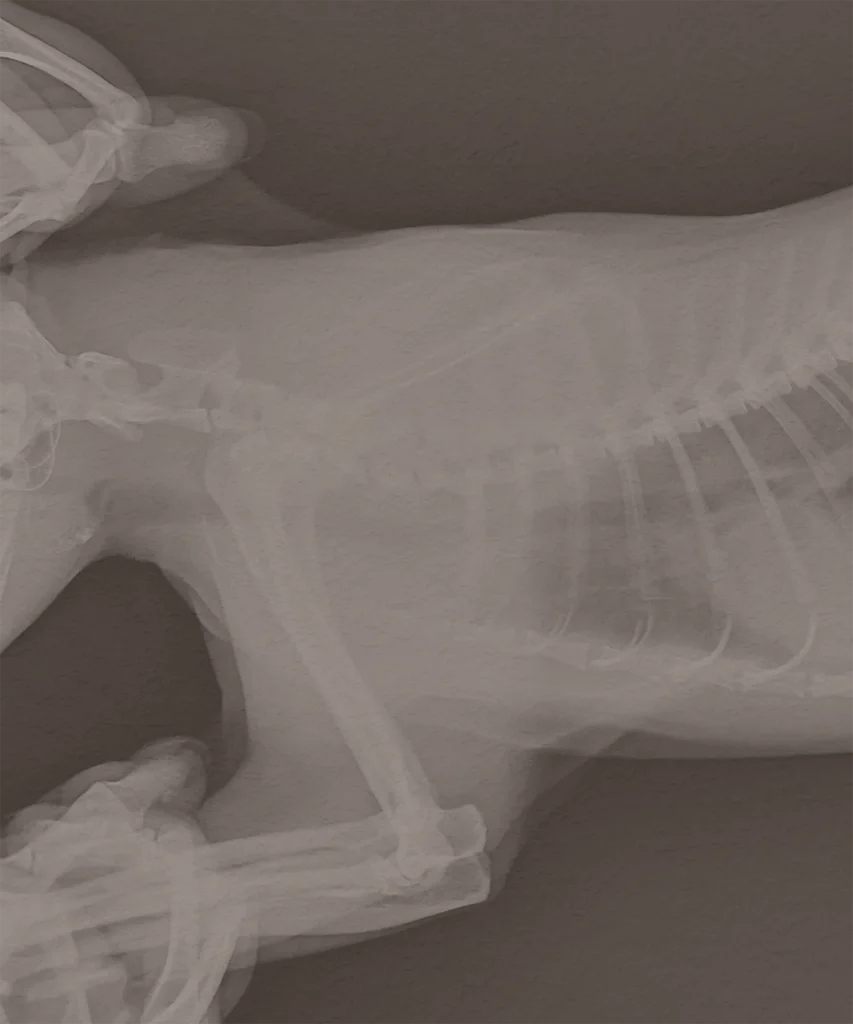

Radiography

This is a commonly used diagnostic tool in veterinary practice, using low level radiation to take images of bone and soft tissue.